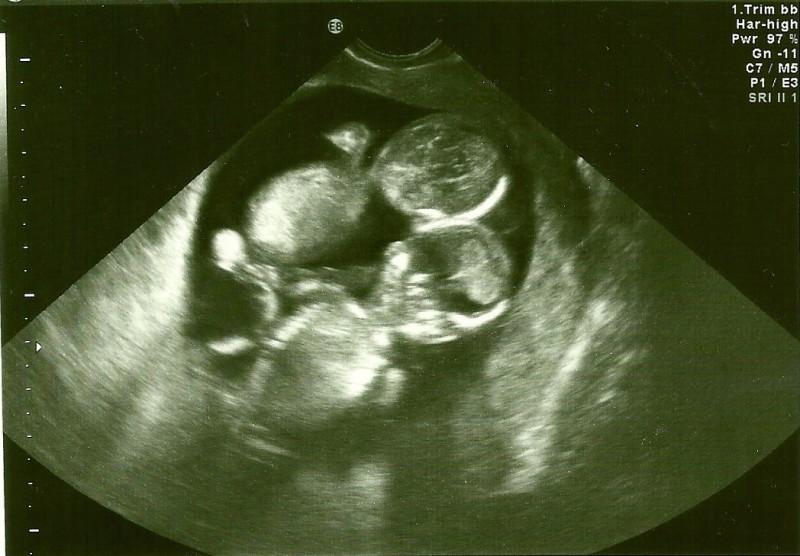

Kate Lucas și soțul ei aveau deja doi copii. Însă ei au hotărât să nu se oprească aici și să mai aducă un micuț pe lume. După ce a făcut testul de sarcină viitoarea mămică nu a fost deloc uimită de rezultatul pozitiv.

A sosit momentul primei ecografii. Fiind copleșită de sentimentele materne și de o fericire absolută, Kate a mers la doctor. Medicul, cu care ea se cunoștea de mult timp, glumea: „Poate ai iarăși gemeni?” Și iată că a ghicit! Într-adevăr, alături de inima lui Kate mai băteau două inimi. Însă, din păcate, această noutate nu a fost singura din acea zi.

Embrionii s-au separat abia după 8-13 zile de la fecundație. De aceea, între ei nu exista o membrană separatoare. Peste câteva zile acești copii puteau deveni gemeni siamezi. Și aceasta este doar o jumătate din problemă!